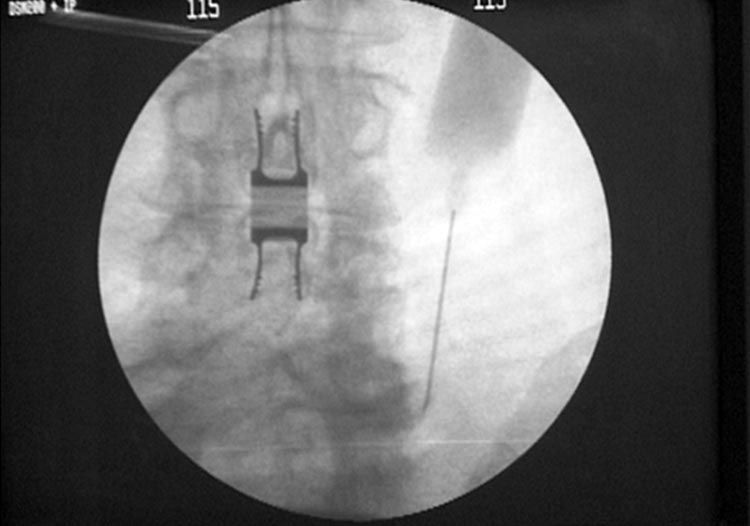

Die Twin Tagesklinik für Wirbelsäulen und Neurochirurgie unter der Leitung von Dr. Al Nahlaoui ist Ihr kompetenter Partner zur Erhaltung der Beweglichkeit sowie Befreiung von Rücken- und Nervenschmerzen.

Moderne Diagnostik und Beratung sowie konservative und operative Behandlung gehören zum umfangreichen Leistungsangebot der Praxis. - www.nahlaoui.de